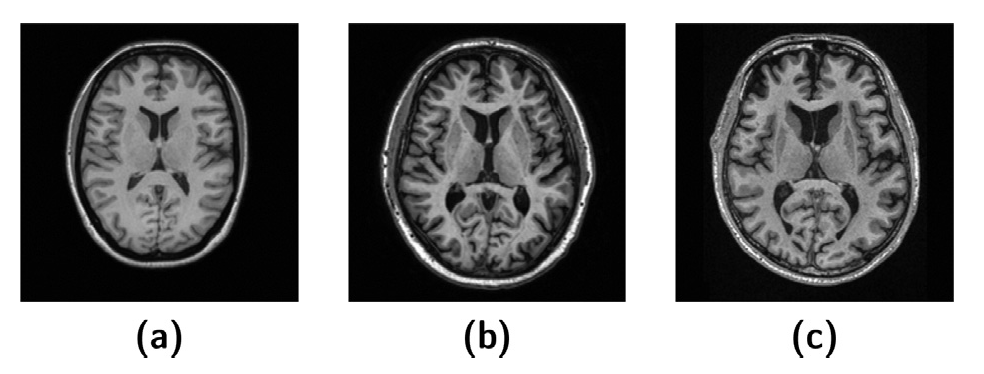

For example, Figure 1 shows us an example of how acquisition parameters make a difference in MRI scans:

Figure 1: T1-weighted MRI images with different acquisition parameters [1]

These variations can sometimes be undesirable. Imagine, we want to build a neural network to predict Alzheimer's disease so we want as much MRI data as possible. But due to dataset variations, two healthy scans from distinct datasets may look more different than a healthy scan compared to a diseased scan from the same dataset. In this case, the amount of data that we can use is limited, which may consequently limit the generalizability or reproducibility of our model.